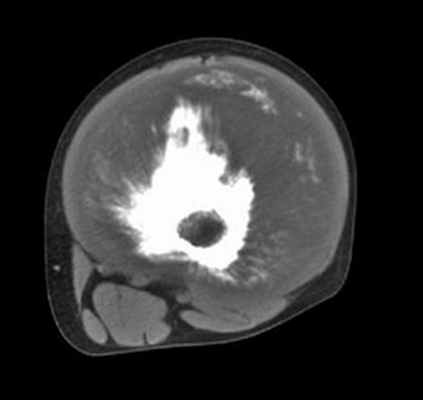

Компьютерная томография позволяет более точно оценить степень деструкции кости и структурные особенности внутрикостного и внекостного компонентов опухоли (рис. 2). КТ органов грудной клетки дает представление о наличии метастазов в легких и лимфатических узлах средостения.

Рис. 2. КТ бедренной кости у больного с остеосаркомой